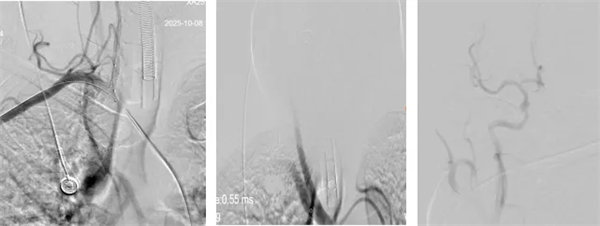

術中,介入團隊精準定位血管閉塞部位,通過微導絲“探路”聯合球囊擴張技術開通右側椎動脈開口,造影椎開口殘余狹窄60%?;讋用}血栓形成,基底動脈管腔狹窄55%,基底動脈尖堵塞,右側大腦后動脈及小腦上動脈未見顯影,左側大腦后動脈P3以遠閉塞。

席聰準確鎖定患者基底動脈處血栓,采用抽吸取栓技術快速開通血管,成功取出堵塞部位2cm的血栓。再次造影示:右側大腦后及雙側小腦上動脈再通,右側大腦后動脈P3段以遠閉塞,考慮慢性閉塞,推注替羅非班,血流明顯加快。隨后采用支架植入術開通右側椎動脈開口處,術中影像顯示:支架貼壁良好,無明顯殘余狹窄,顱內血管顯影良好。